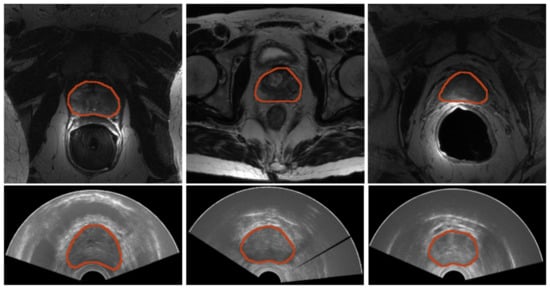

Quantitative results for MRI segmentation with nnU-Net are reported in Table 2, and the qualitative results, as segmentation masks, are depicted in Figure 8. The nnU-Net model trained on the PROMISE12 challenge obtained the best results [14,15]. The SAML-V dataset was obtained by sampling 24 images for validation from the SAML dataset. It is worth noting that the Dice coefficient is higher than 88% and ASSD is less than 1 mm for both validation sets under consideration, showing the reliability of the nnU-Net framework for the automatic MRI segmentation of the prostate region.

Figure 8.

Results for prostate segmentation from MRI. Top row contains images from the SAML dataset and the second row contains images from ZENODO. The ground truth is represented in red, whereas the predictions from the nnU-Net models are colored in green. The middle image shows the prediction mask for the nnU-Net trained for only 10 epochs, whereas the right image depicts the prediction mask for the one trained on the PROMISE12 dataset.